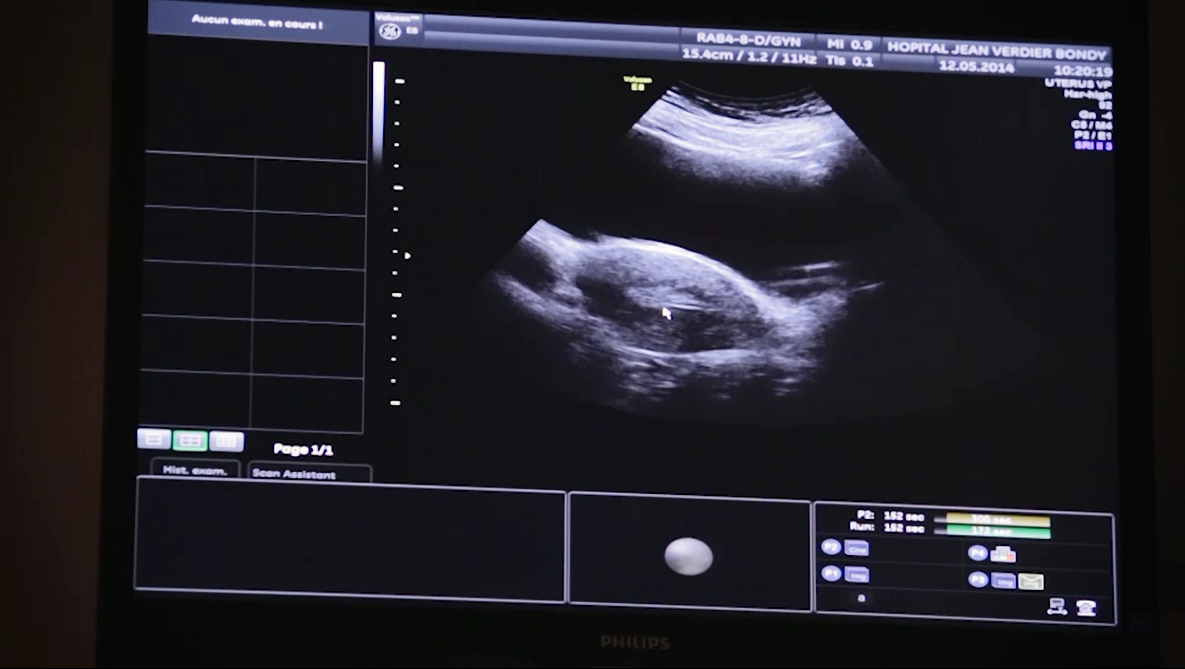

Après recueil d’ovocytes par stimulation ovarienne ou par maturation in vitro (MIV), les ovocytes peuvent être fécondés au laboratoire en injectant un spermatozoïde directement dans l’ovocyte mature (injection intracytoplasmique de spermatozoïdes). Environ 60% des ovocytes fécondés donnent lieu à un embryon. Les embryons sont congelés (vitrification) après un délai de 24 à 48 heures. Les taux de survie après dévitrification sont de l’ordre de 90%. Le nombre d’embryons conservés est précisé par le biologiste de la reproduction. La patiente est contactée chaque année pour savoir si elle souhaite poursuivre la conservation des embryons. La conservation des embryons ne peut être proposée qu’aux femmes ayant un conjoint masculin. En cas de séparation, la femme ne pourra pas avoir accès aux embryons. Au moment de la mise en œuvre d’un projet de grossesse, une demande des deux membres du couple est nécessaire pour pouvoir décongeler des embryons. En accord avec le médecin, le transfert d’embryon dans l’utérus de la patiente, après stimulation hormonale, peut être réalisé.